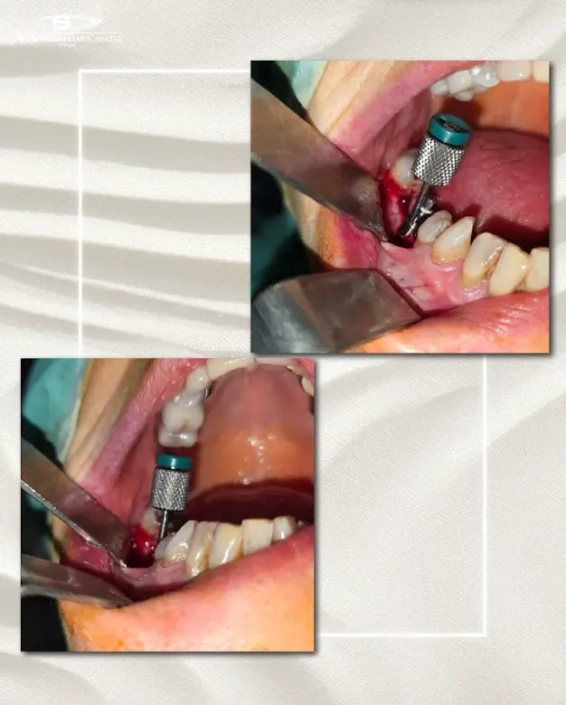

Cas clinique du Dr. Benat avec les Implants Co-Axis®

Le cas clinique met en évidence une insuffisance de volume osseux avec un axe implantaire défavorable en secteur postérieur, objectivée sur l’imagerie 3D et la radiographie panoramique, compromettant un positionnement implantaire axial conventionnel sans compromis prothétique.

Avec la collaboration du Dr. Gauthier Benat